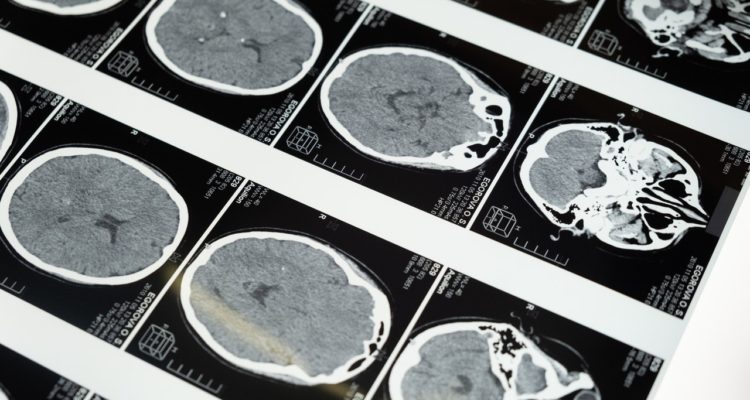

Covid-19 reduciría el volumen de la materia gris del cerebro, según estudio